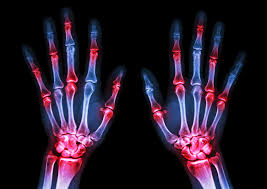

Reumatoidalne zapalenie stawów (RZS) wbrew panującym stereotypom atakuje ludzi młodych pomiędzy 30. a 50. rokiem życia. Występuje 3-krotnie częściej u kobiet i dotyczy 0,9% populacji ludzi dorosłych w Polsce. Choroba przynosi ból i ogranicza sprawność fizyczną. Towarzyszą jej stałe zmęczenie, obniżony nastrój, stany lękowe a nawet depresja, które przez otoczenie chorych mogą nie być uznawane za istotne, tymczasem dla samych pacjentów okazują się być wręcz kluczowe. RZS to choroba nieuleczalna, a jednym z głównych celów leczenia jest profilaktyka niepełnosprawności rozwijającej się w trakcie trwania choroby.